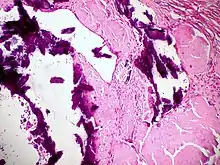

Amyloidosis, blood vessels, H&E

Amyloidosis, lymph node, H&E

Cardiac amyloidosis. H&E stain.